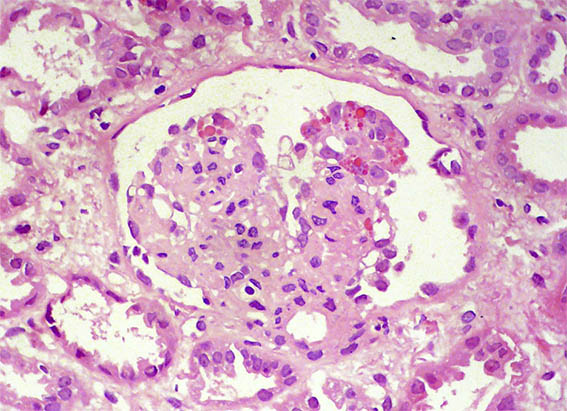

Figure 1. H&E, X100.